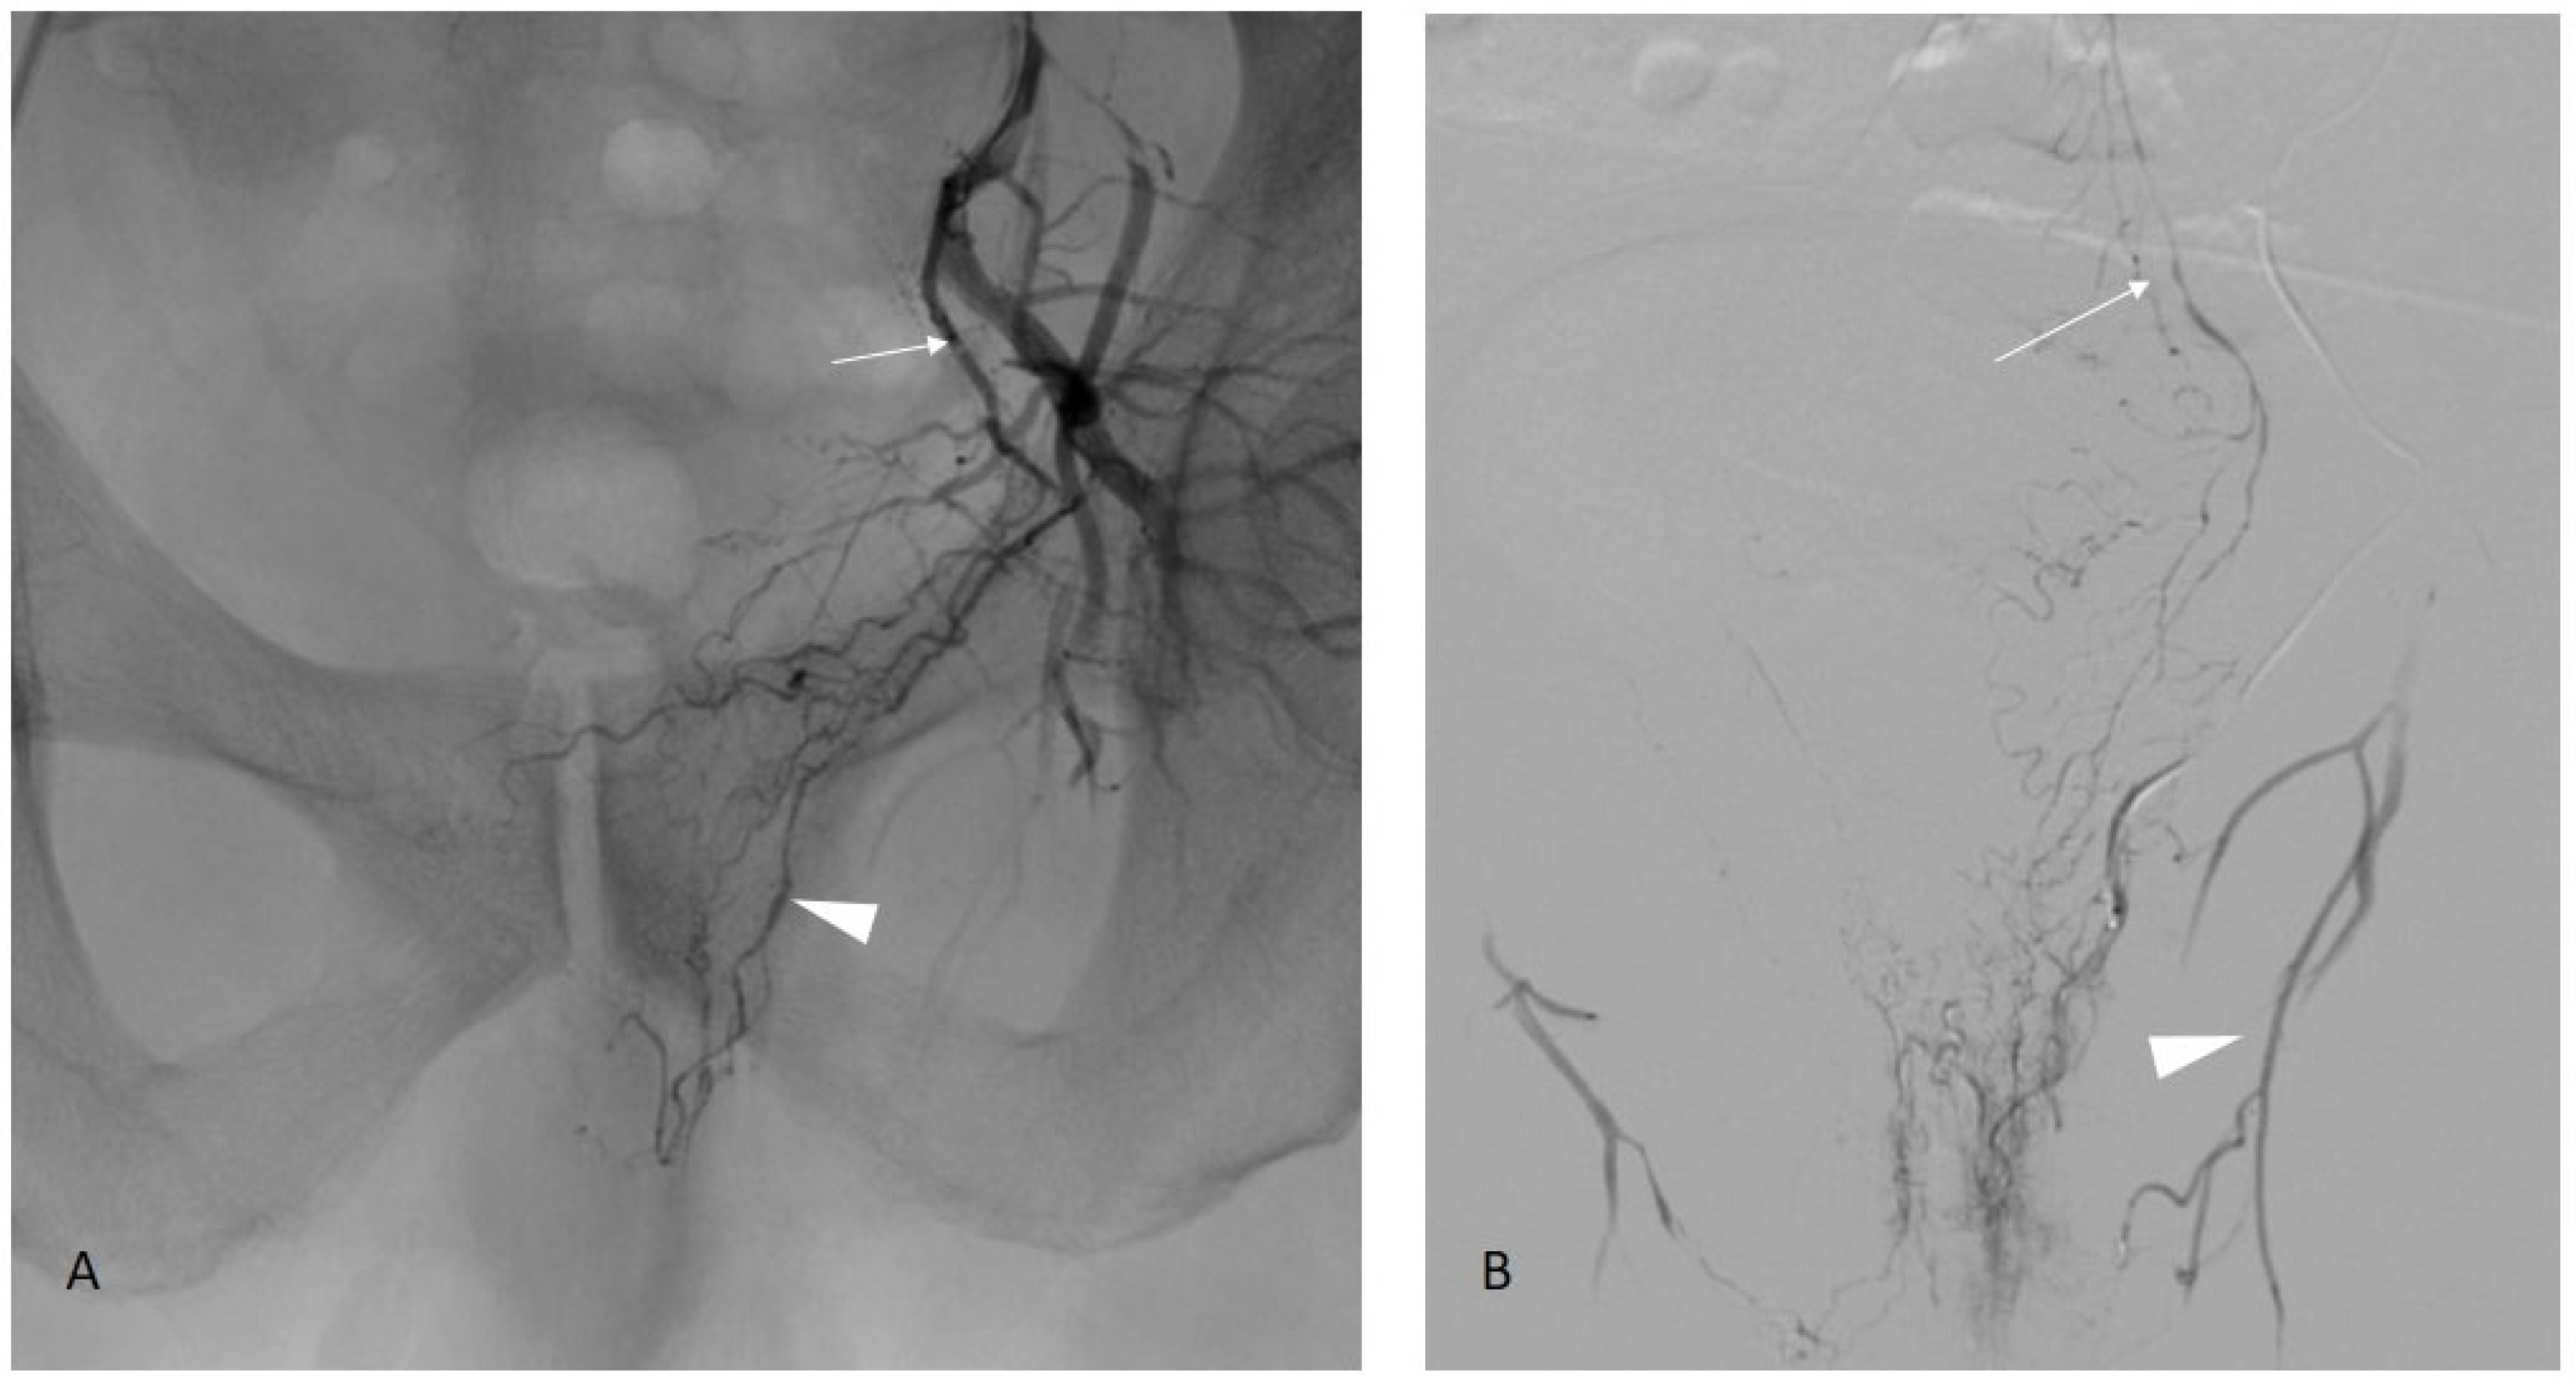

Figure 5.

Prostate artery connection with the middle rectal artery. Image (A): Iliac angiography demonstrating a vesico-prostatic trunk (arrow) with collateral in the direction of the rectum (arrowhead). Image (B): Supraselective angiography in the middle rectal artery confirming the opacification of the rectum and connection with the superior rectal artery (arrow) arising from the inferior mesenteric artery. Note another shunt with the obturator artery (arrowhead).